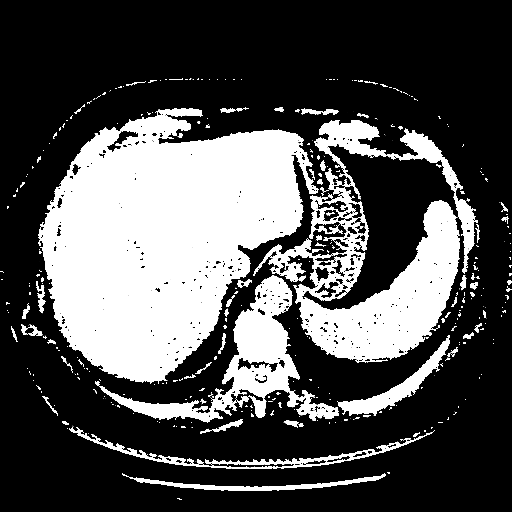

Image Grid

4Γ—3 grid: Rows show different image types (Original NATIVE, Reconstructed NATIVE, Original VENOUS, Generated VENOUS), Columns show windowing techniques (No Window, Lung Window, Mediastinum Window)

Original VENOUS CT scan

Full window (WL 1023.5, WW 4095 β†’ Low βˆ’1024, High +3071)

Actual HU range: [-1024.0, 3071.0]

Lung window (WL -600, WW 1500 β†’ Low βˆ’1350, High +150)

Actual HU range: [-1350.0, 150.0]

Mediastinum window (WL 40, WW 400 β†’ Low βˆ’160, High +240)

Actual HU range: [-160.0, 240.0]